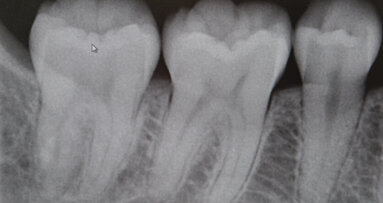

HAMILTON, Kanada – Wie es um die eigene Vitamin-D-Versorgung bestellt ist, lässt sich anhand von Zahnröntgenaufnahmen ablesen, wie kanadische Forscher ...